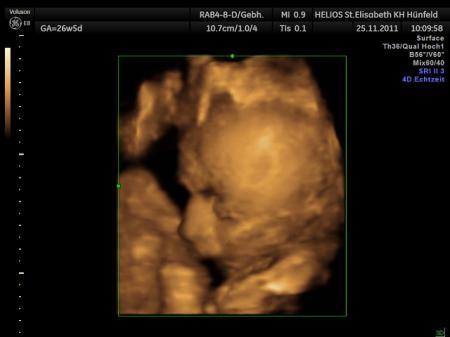

Halli hallo Waren heute auch wieder zur vu und zum 3.screening. Mein kleiner wiegt 2100g und ist schon 47cm groß Ich weiß garnicht wo die größe her kommen soll, ich bin schließlich nur 1,62m und mein freund 1,66m. Meine tochter kam mit 47cm in der 39.ssw zur welt, das maß hat er ja jetzt schon. Fa war aber sehr zufrieden und fand das nicht zu groß. Na mal abwarten ;-) Und mein gefühl neulich war richtig, er hat sich unmittelbar nach dem letzten fa-termin in sl gedreht :-) Ach und die waage hat gesagt, dass ich 14kg mehr hab jetzt Lg anja

Bild zu